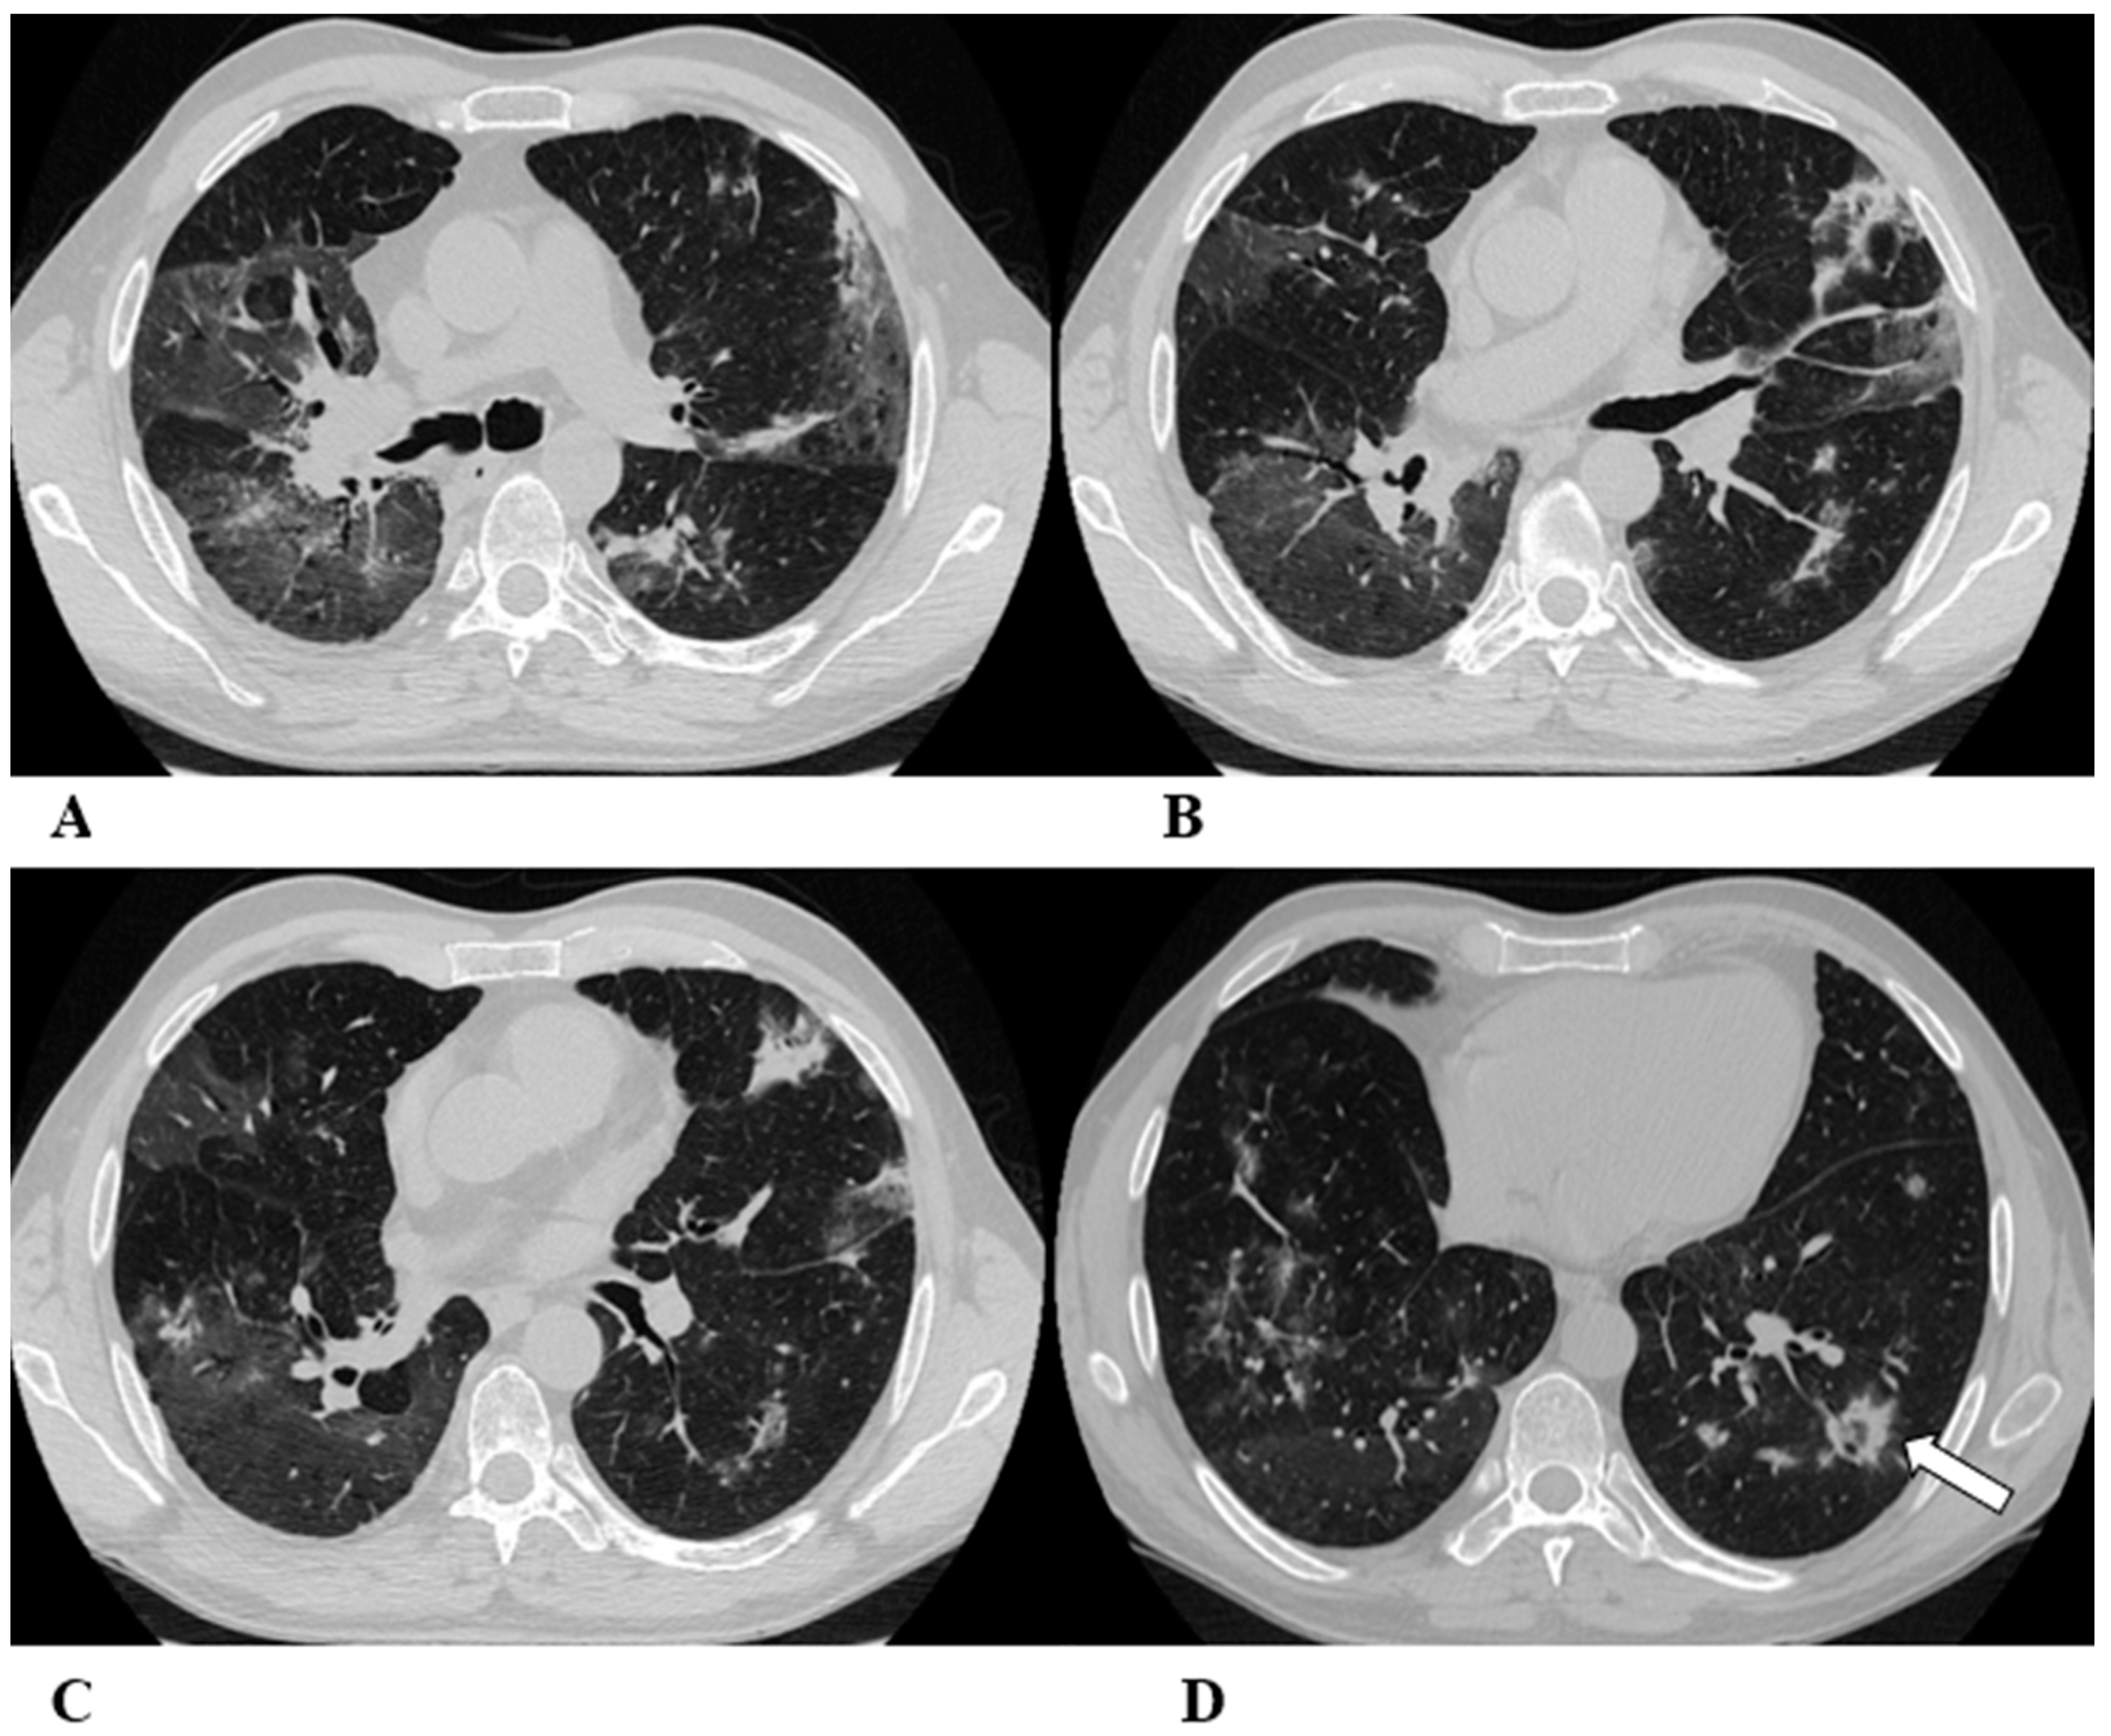

Figure 2.

Non-specific interstitial pneumonia (NSIP). Non-specific interstitial pneumonia represents the second most commonly described pattern of ICI-related pneumonitis. It is defined pathologically by different degrees of interstitial inflammatory cell infiltrates and/or fibrosis. HRCT characteristics in patients with NSIP consist of GGOs associated with irregular reticulations and traction bronchiectasis/bronchiolectasis. Honeycombing is infrequent and minimally represented. NSIP distribution is usually bilateral and symmetric, predominantly subpleural and basal, and often with sparing of the immediate subpleural lung.

The NSIP pattern should be distinguished from atypical pneumonia based on clinical analysis. The greater involvement of the lung bases and recurrent relative subpleural sparing must be considered in the clinical assessment of the patient, as they are uncommon findings in infectious processes. It is also necessary to exclude the concomitance of immune disorders and connective tissue diseases [9,12].

(A–D) A 70-year-old man with lung adenocarcinoma and brain metastases treated with pembrolizumab, carboplatin and pemetrexed as first-line treatment. Two months later, the patient had dyspnea and dry cough, without fever.

Axial chest CT scans show mild subpleural reticulation in the lower lobes (black arrows (A,B,D)) and patchy bilateral and partially confluent areas of GGO in both lungs predominant in the lower lobes (white arrows (B,C)). Incidental findings: rare small lucent areas of centrilobular emphysema, especially in both upper lobes.